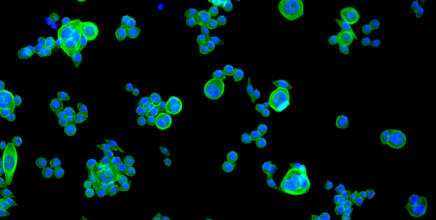

Cancer du sein: pourquoi les métastases gagnent les os

Vaincre les résistances au traitement du cancer du sein